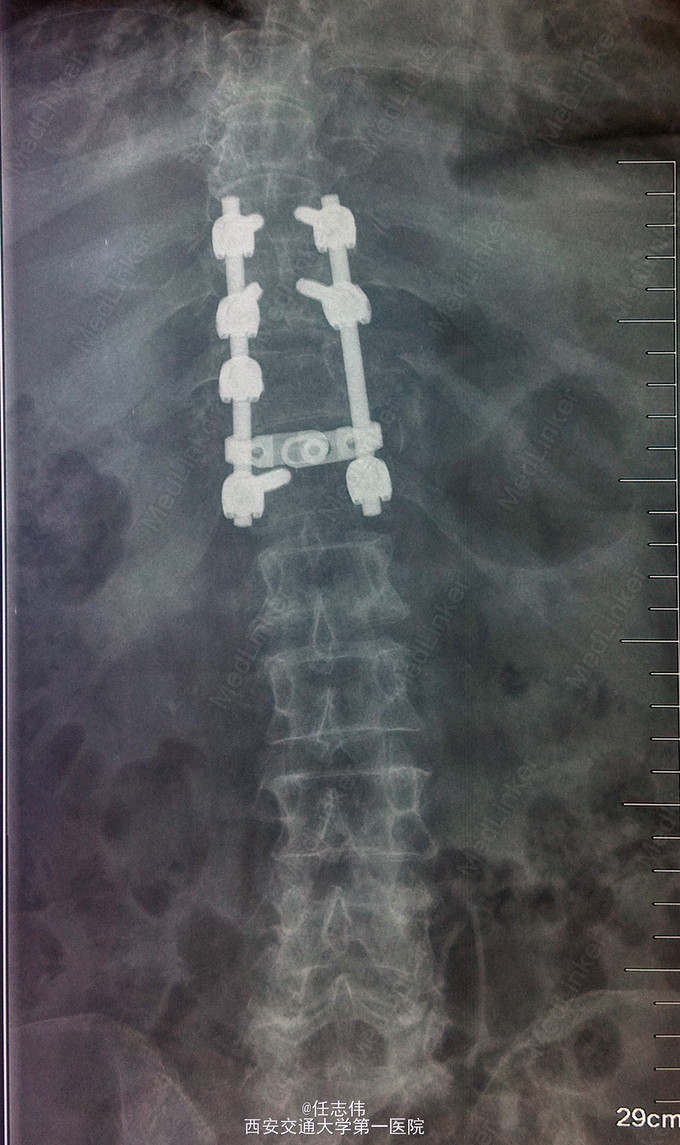

诊断:1.胸11椎体骨折伴截瘫(Frankel A级)2.闭合性胸部损伤,肺挫伤,多发肋骨骨折,双侧胸腔积液 处理:1.急诊入院告病危,心电血氧监护;2.予以甲强龙冲击治疗;3.次日复查胸部CT,查看肺部损伤情况及胸腔积液,后予以右侧放置闭式引流。患者氧合不稳定,2日后复查胸片胸腔积液减少,予以行后路减压内固定融合术。 手术:术中见局部软组织损伤严重,胸11-12棘上、棘间韧带断裂,胸10、11、12双侧关节突有骨折移位,胸11椎板骨折,胸11左侧不能置入椎弓根螺钉,遂行单纯固定。脊髓局部挫伤明显,并有硬膜破损,予以处理。

术后患者逐渐病情平稳,拔出闭式引流。伤口愈合好。 查体双下肢深感觉有恢复,但肌力仍0级,巴氏征阳性。 1.在没有CT检查时,此骨折容易漏诊,需要注意询问病史,完善检查,尤其是无神经损伤表现者。 2.此患者固定范围应该扩大到腰1吗?还是至胸12就可以了,病椎大家一般都固定吗? 3.对于此例患者大家都急诊手术吗?还是要先处理肺部情况。